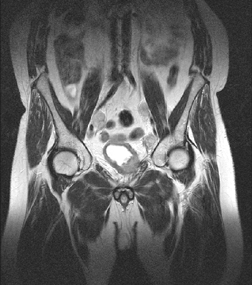

МРТ более 10 лет применяется для диагностики РМП. Преимущество перед РКТ состоит в более высоком (в 70 раз) контрастном разрешении. Кроме того, исследование производится в трех плоскостях — аксиальной, фронтальной и сагиттальной, вследствие чего получается более полное представление об опухоли и ее взаимоотношениях с окружающими органами (рис. 5). Качество исследования значительно повышается, если его производить с парамагнитным контрастным средством (гадопентеновая кислота, гадодиамид). Это позволяет значительно усилить интенсивность изображения опухоли. При использовании контрастного усиления точность МРТ в определении опухолевого поражения в стадии рТ3 составляет более 80%, тогда как при исследовании без контрастирования она равна 50–60%. МРТ не всегда позволяет обнаружить опухоли размером до 1 см. Ограничены возможности МРТ и в дифференцировании поверхностных опухолей от инвазивных (Т2). Наиболее эффективно это исследование, во-первых, при инвазивных новообразованиях, инфильтрирующих паравезикальную клетчатку, а, во-вторых, при диагностике регионарных метастазов.

Рисунок 5. МРТ-снимок

На снимке органов таза во фронтальной проекции в нижних отделах мочевого пузыря определяется опухоль неправильной формы сниженной интенсивности сигнала в T2. По ходу подвздошных сосудов отмечаются увеличенные лимфоузлы